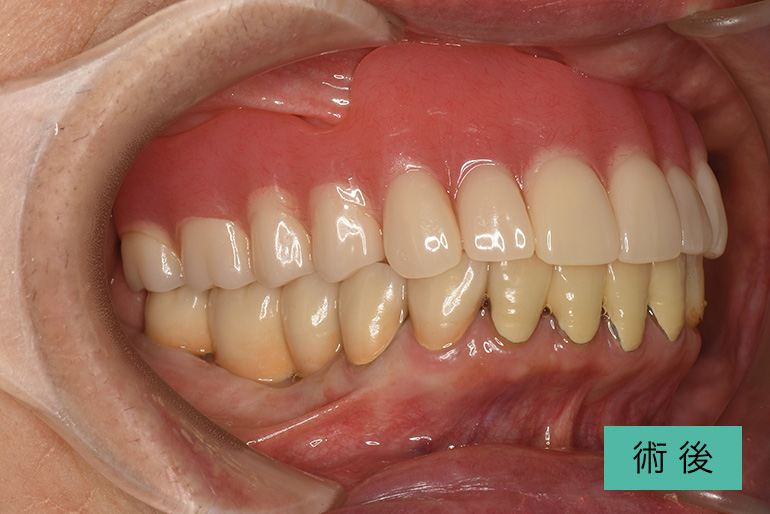

| 治療内容 | 上顎前歯右上3番から左上3番のセラミック冠 |

| 治療期間・回数 | 約1ヶ月、3回 |

| 費用(税込) | ¥990,000(165,000/1本)(補綴費用) ※自由診療 |

| リスク・副作用 | 疼痛、補綴物の脱落、咬合違和感、破折 |